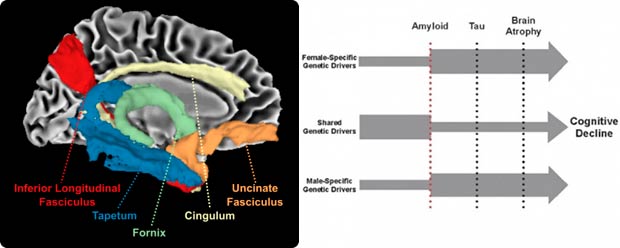

Computational neurogenomics

Our work is focused on Alzheimer's disease (AD) risk, resilience, and sex differences. Through transdisciplinary collaboration, we seek to facilitate a more rapid move from genomic discovery to therapeutic development. We have identified molecular drivers of resilience through genomic and proteomic analyses leveraging neuroimaging and neuropathology endophenotypes, and we integrate these diverse data types into a precision medicine approach, focusing on characterizing the best predictors of risk and resilience given an individual’s age, sex, genetic, and neuropathological context.